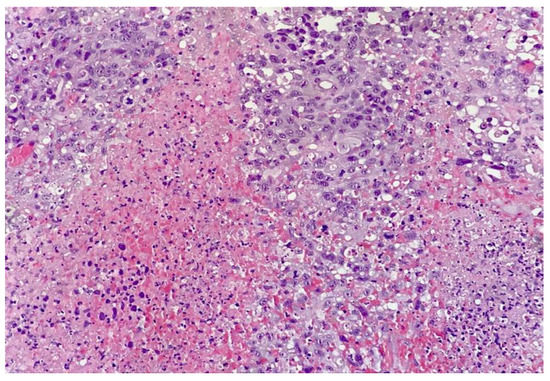

2. Case Report and Evolution